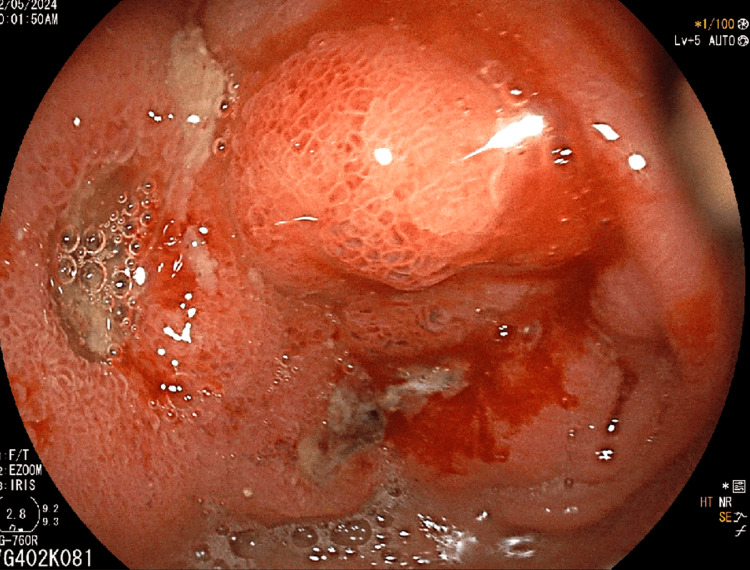

Imaging studies, including ultrasound and CT scan, identified a mass in the caudate lobe of the liver with dilated intrahepatic bile ducts (Figures 1A, 1B), encroaching on the duodenum (Figure 1C), and CBD (Figure 1D), causing partial gastric outlet obstruction and obstructive jaundice. PET-CT (Figure 2) confirmed persistent abnormally increased fluorodeoxyglucose (FDG) uptake in a hypo-enhancing lesion at the post-operative site in the caudate region, infiltrating the first and second parts of the duodenum with luminal narrowing and showing effacement of fat planes with the portal vein and inferior vena cava (IVC). The lesion also abutted the head of the pancreas with suspicious loss of the fat plane, measuring approximately 66 x 68 mm (SUVmax 14.8). Persistent abnormally increased FDG uptake was also noted in a hypo-enhancing lesion involving the splenic parenchyma adjacent to the hilum, measuring 28 x 20 mm (SUVmax 4.2). Upper GI endoscopy with side view scope (esophagogastroduodenoscopy (EGD)) revealed external compression on the duodenum with D1 mucosa edematous, erythematous with superficial ulceration causing D1 and D2 narrowing, corroborating the imaging findings of partial gastric outlet obstruction (Figure 3).